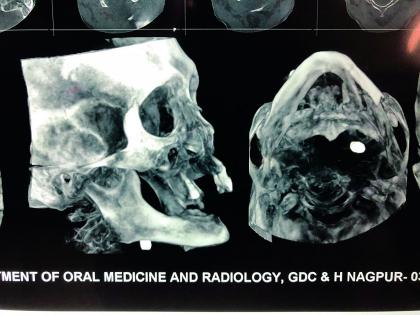

गुंतागुंतीची शस्त्रक्रिया

मुख शल्य चिकित्सक विभागाचे प्रमुख डॉ. अभय दातारकर म्हणाले, सदाराम ठाकूर यांच्या डाव्या गालातून बंदुकीची गोळी आत शिरली. खालचा जबडा चिरत ती मानेजवळ येऊन फसली. ‘एक्स-रे’मध्ये गोळी कुठे आहे हे दिसत असले तरी कुठल्या टिश्यूमध्ये आहे हे शोधणे कठीण होते. शस्त्रक्रियेला सुरुवात केली तेव्हा ही गोळी मेंदूला रक्तपुरवठा करणाऱ्या वाहिनीजवळ होती. यामुळे मोठ्या शिताफीने ही गोळी काढावी लागली. गोळी काढल्यानंतर सदाराम ठाकूर यांचा चकनाचूर झालेल्या जबड्यावर शस्त्रक्रिया करून ‘रिकन्स्ट्रक्शन’ करण्यात आले.